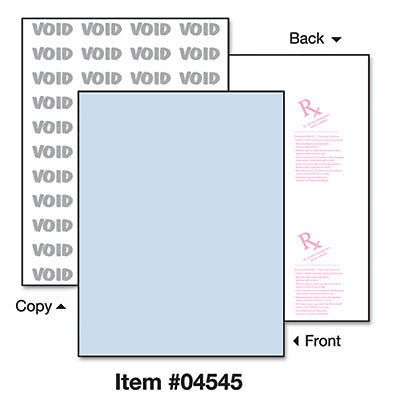

DocuGard Security Paper, 24lbs, 8-1/2 x 11,Blue, 500/Ream, Sold as 1 Ream